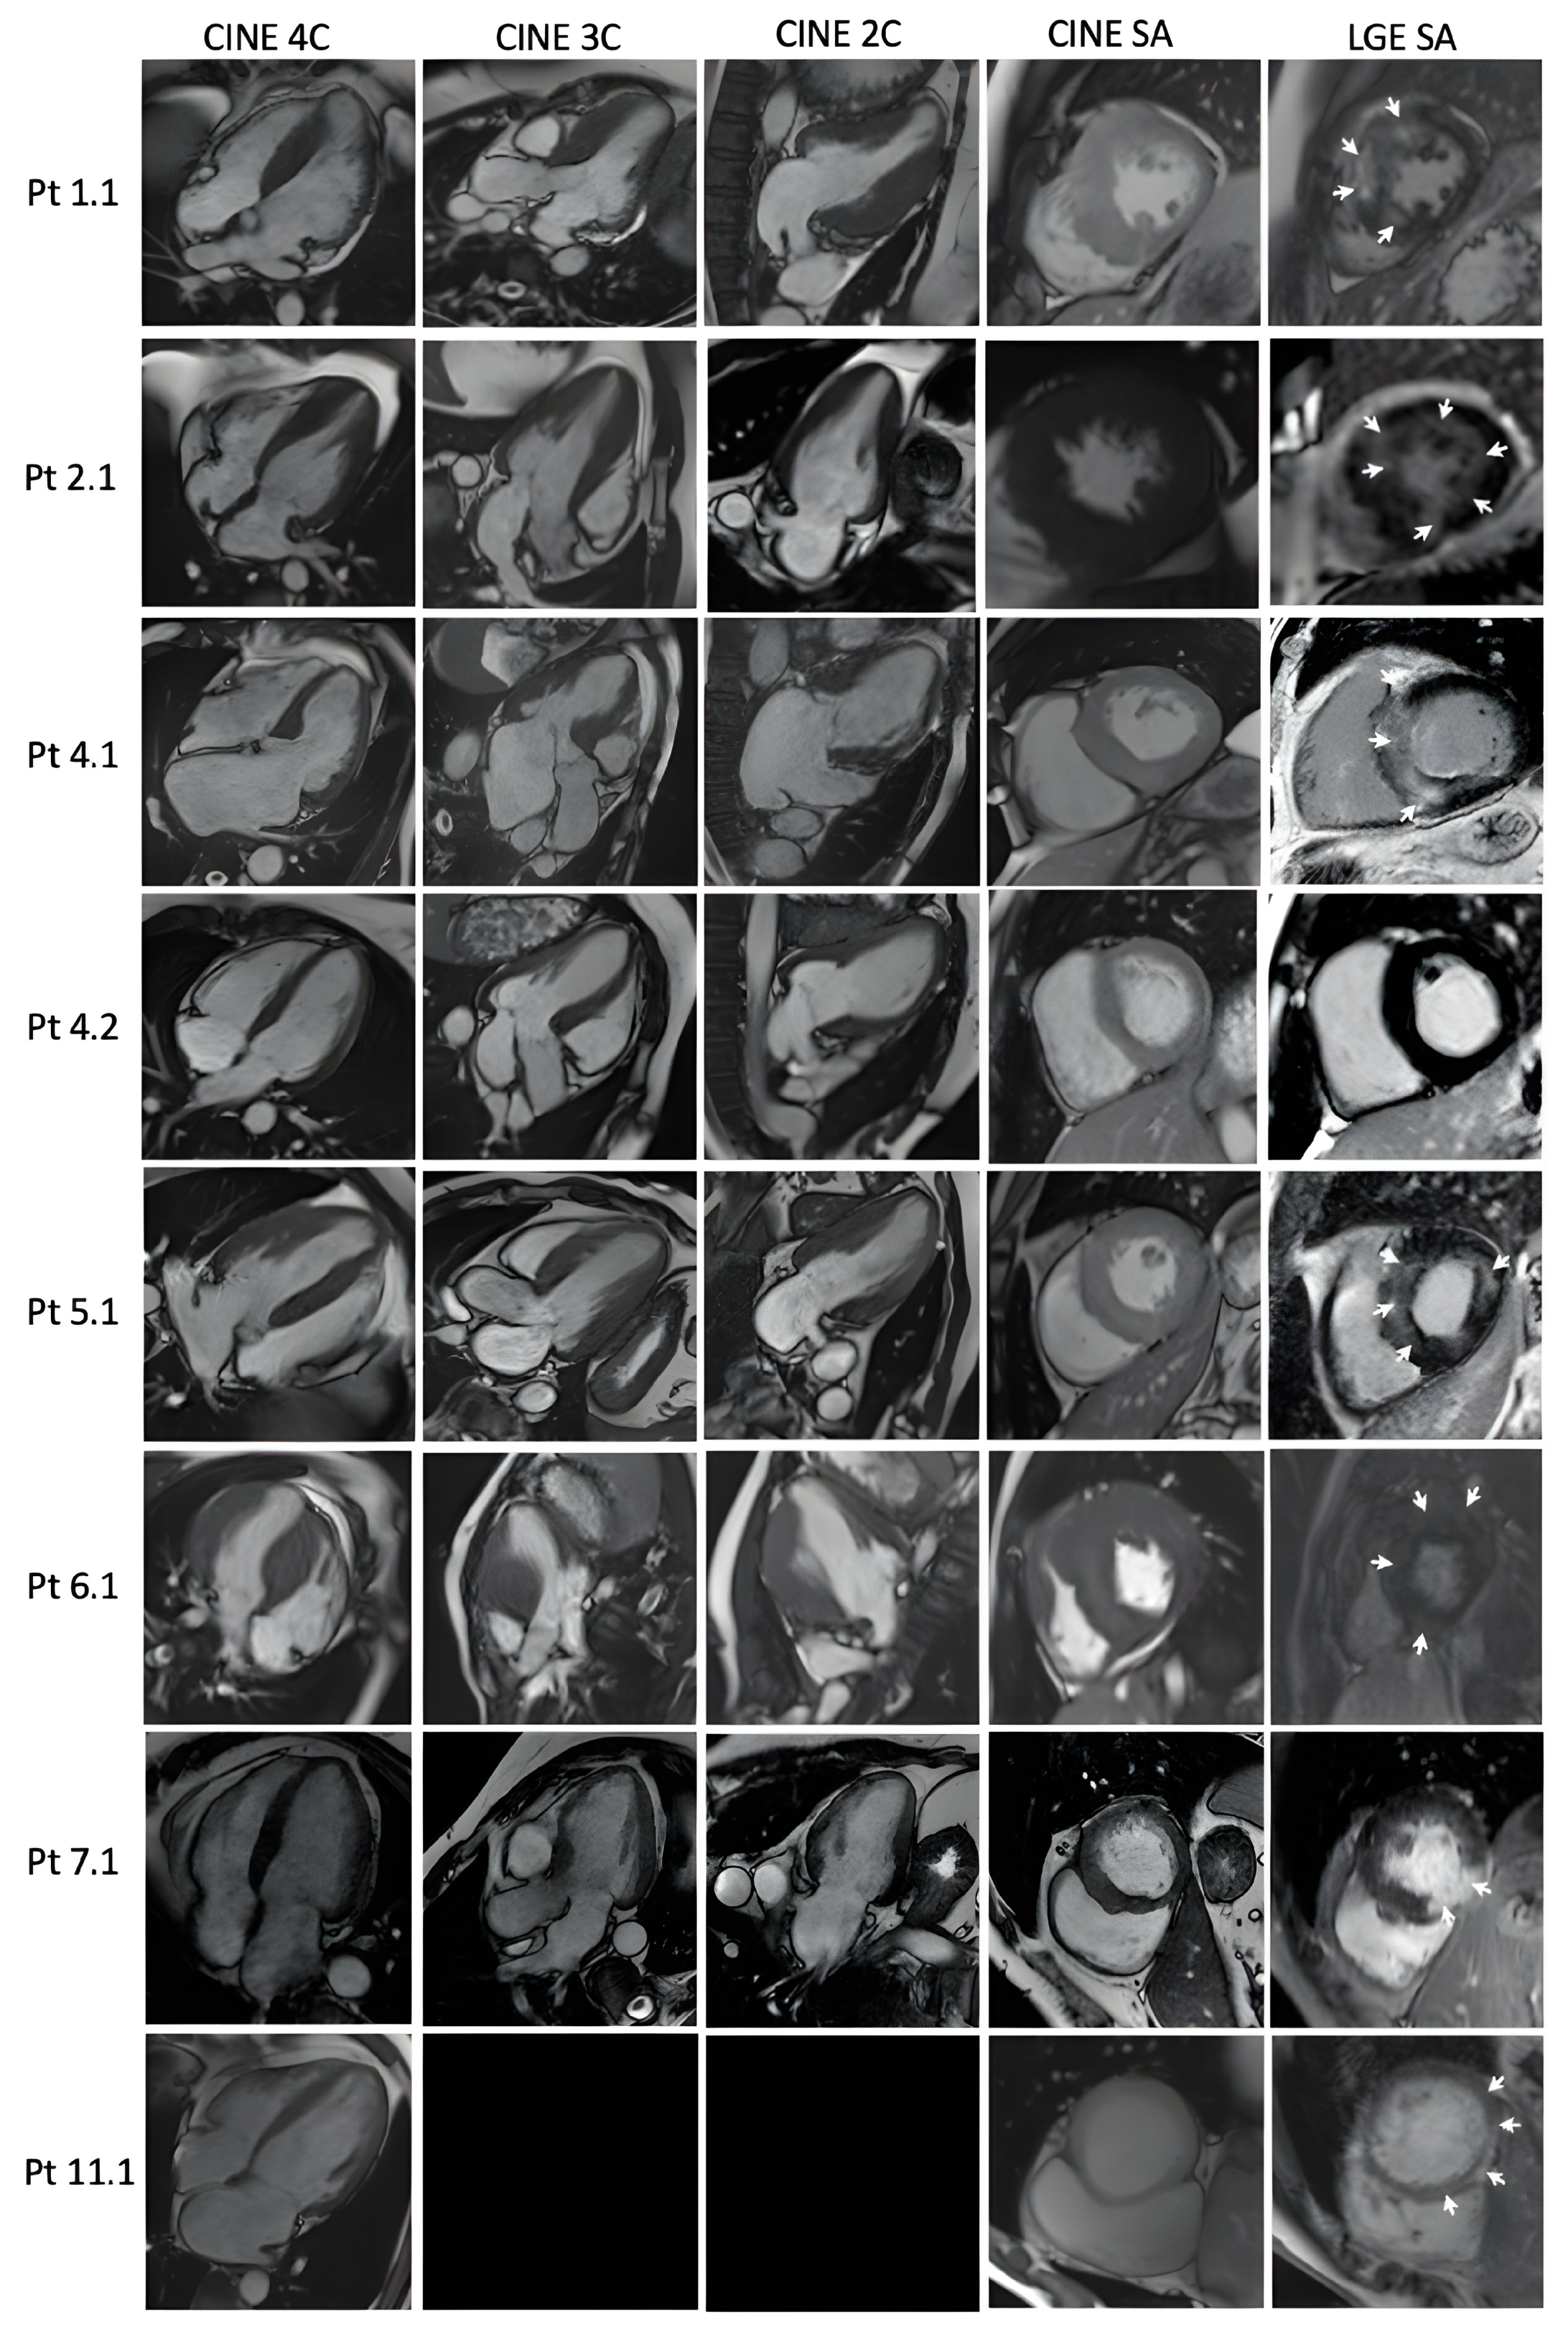

| LGE | + | + | + | - | + | + | + | + | + |